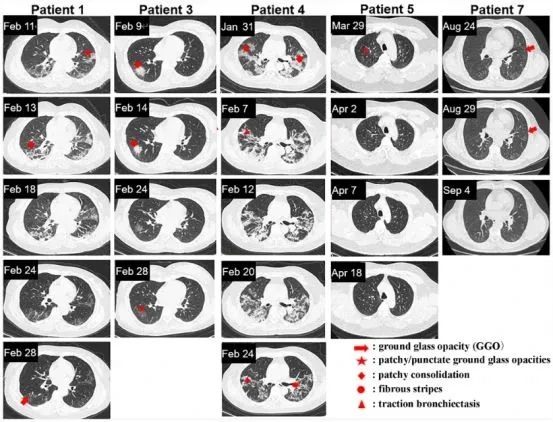

其他五名患者的 CT 圖像如下圖所示,能發現從一開始就接受外泌體治療的人(患者 5、7)和抗病毒治療一段時間后再接受外泌體治療的人(患者 1、3、4)在肺部病變完全吸收的時間之間存在顯著差異。

注:患者 1、3、4、5 和 7 的胸部 CT 圖像